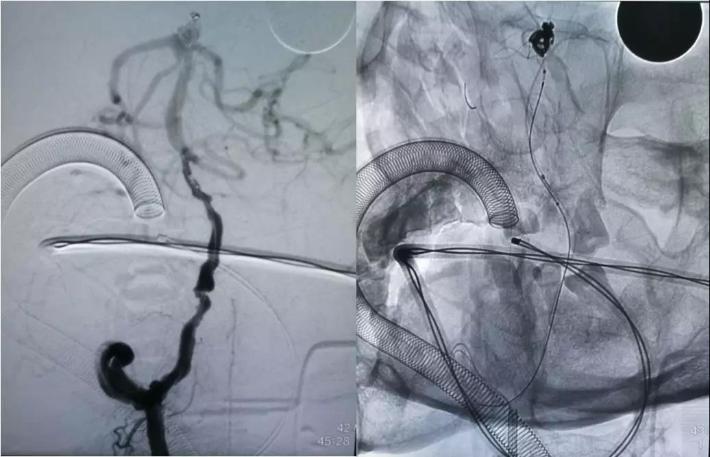

采用支架推挤技术,推挤支架,保护双侧大脑后动脉、右侧小脑上动脉,继续将动脉瘤填塞致密,完全打开支架

处理右侧颈内动脉虹吸段夹层动脉瘤。

预置入支架导管,栓塞动脉瘤用微导管头端超选进入动脉瘤腔,通过支架导管送入Enterprise支架(4.5*22mm)并打开支架,填入弹簧圈栓塞夹层动脉瘤。但此时发现大脑前动脉A1段不显影。